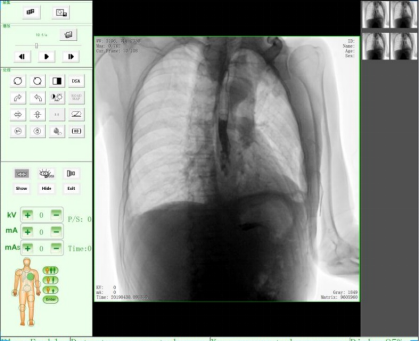

隨著人們健康意識(shí)不斷提高,越來(lái)越多人重視健康體檢,而數(shù)字化DR拍片幾乎是體檢必檢項(xiàng)目之一,胸片結(jié)果正常DR報(bào)告顯示為:胸廓對(duì)稱(chēng),兩側(cè)肋骨、肋間隙正常;兩肺紋理清晰,未見(jiàn)明顯實(shí)質(zhì)性浸潤(rùn);兩側(cè)肺門(mén)和縱隔影來(lái)見(jiàn)明顯異常;心臟大小、形態(tài)在正常范圍內(nèi);膈肌平滑,雙側(cè)肋膈角銳利時(shí),則說(shuō)明您一切正常。那么,數(shù)字化DR胸片報(bào)告不正常的結(jié)果有哪些呢?

3、兩肺紋理增粗、紊亂,呈網(wǎng)狀或條索狀、斑點(diǎn)狀陰影。

老慢支,肺氣腫,肺心病,這時(shí)您的數(shù)字化DR片可能會(huì)呈現(xiàn)這種胸片,當(dāng)進(jìn)一步發(fā)展時(shí),將會(huì)出現(xiàn)兩肺透亮度增加。由于肺泡過(guò)度通氣致使X光胸片上黑化度增加,即越黑透亮度越大。哮喘發(fā)作時(shí)同樣可見(jiàn)兩肺透亮度增加,呈過(guò)度充氣狀態(tài)。當(dāng)然,X線攝影條件過(guò)高或是顯影時(shí)間過(guò)長(zhǎng)也會(huì)導(dǎo)致這樣。

如果臨床表現(xiàn)為在原有咳嗽、咳痰的基礎(chǔ)上有逐漸加重的呼吸困難,甚至有胸悶、氣急、桶狀胸。常見(jiàn)的嚴(yán)重肺氣腫、肺大泡還會(huì)導(dǎo)致氣胸,也就是胸腔內(nèi)的氣體將肺壓縮,使被壓縮的肺與胸壁間出現(xiàn)透明的含氣區(qū),其中不見(jiàn)肺紋理。這些多是由白變黑的異常。